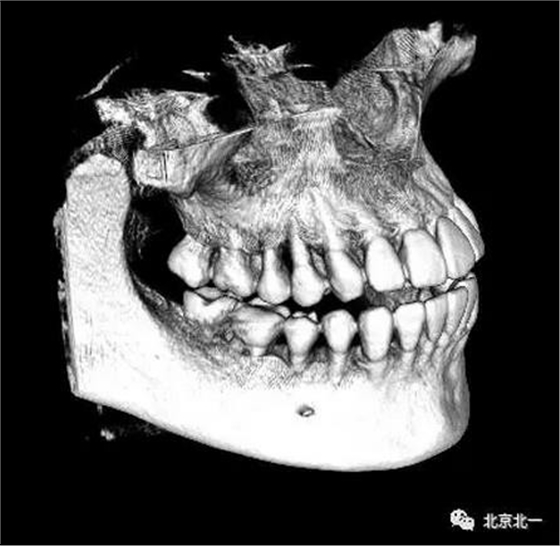

圖四:三維重建

圖五:三維重建可見牙冠突破舌側